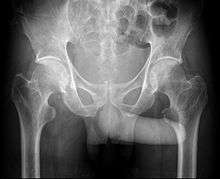

The John Thomas sign,[1] also known as the Throckmorton sign,[2] is a slang or joke term used in the field of radiology. It refers to the position of a penis as it relates to pathology on an x-ray of a pelvis. When the penis (visible on the x-ray as a shadow) points towards the same side as a unilateral medical condition such as a broken bone, this is considered a "positive John Thomas sign", and if the shadow points to the other side, it is a "negative John Thomas sign."[3]

Studies have shown that the "sign" is no better than chance at identifying the location of a hip fracture.[4][5] One such study concluded that "The use of John Thomas sign remains limited to introducing humorous atmosphere in orthopedic meetings as the sign is clinically unreliable."[6] In those cases where the John Thomas sign is positive, it has been proposed that a person with a displaced hip fracture may try to lie on the injured side to immobilize the fracture and reduce pain; the penis then inclines toward the downward (injured) side.[7]